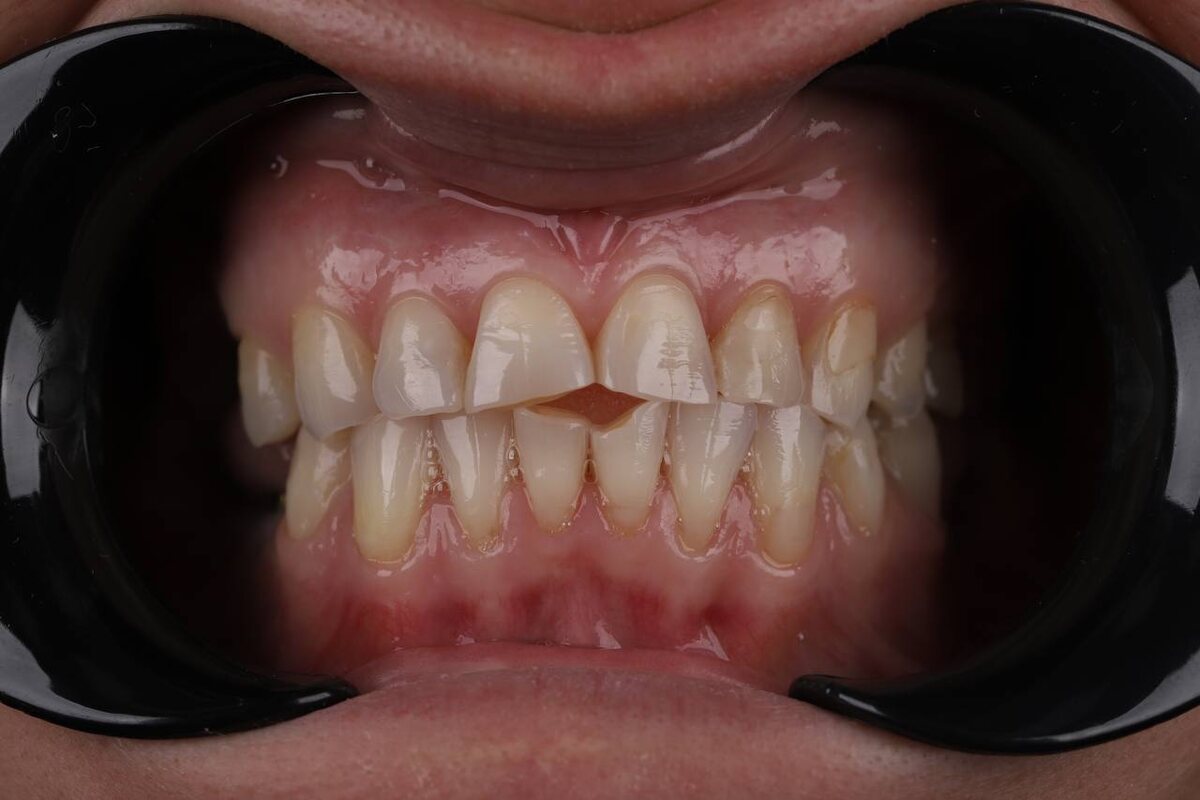

Какая ситуация была изначально?

• Стираемость зубов

• Были зубы с хроническим воспалением

• Некоторые зубы отсутствовали

• Эстетические дефекты

Фотография до лечения